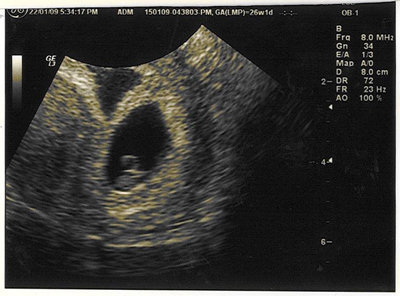

Tisz: a Te babád is szép nagy már

jövő csütörtökön megyünk mi is UH-ra, a mi babócánk is kb ekkora lesz majd